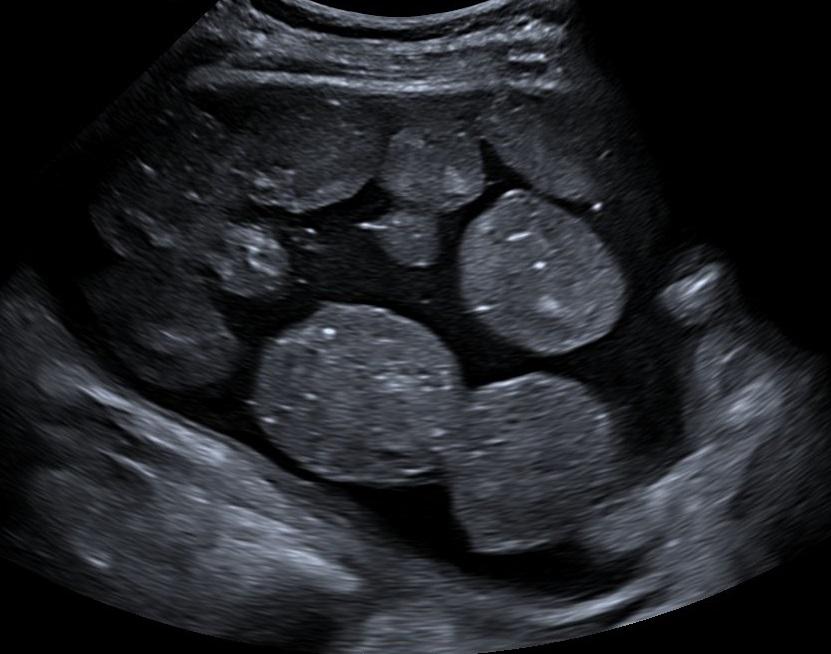

Echo van een cyste.

Bij een 34-jarige vrouw wordt bij toeval een zwelling in de onderbuik ontdekt. Echografisch onderzoek laat een cyste van het rechter adnex zien. In de cyste bevinden zich meerdere solide, niet-gevasculariseerde, bolronde afwijkingen met een diameter van circa 5 cm.